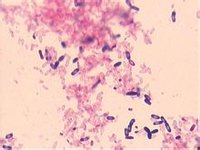

難辨梭狀芽孢桿菌梭狀芽孢桿菌包括一大群厭氧或微需氧的粗大芽孢桿菌。革蘭染色陽性,芽孢呈圓形或卵圓形,直徑大於菌體,位於菌體中央,極端或次極端,使菌體膨大呈梭狀,故得名。

梭狀芽孢桿菌(1)形態結構:革蘭陽性粗大桿菌,芽胞位於次極端,呈橢圓形,直徑小於菌體。在機體內可形成明顯的莢膜。 (2)培養:厭氧不嚴格,繁殖周期僅為8分鐘,在血瓊脂平板上可形成雙層溶血環,內環是由θ毒素引起的完全溶血,外環是由α毒素引起的不完全溶血。(3)生化反應:非常活躍。典型的有:1)“Nagler反應”:在卵黃瓊脂平板上,菌落周圍出現乳白色渾濁圈,是由細菌產生的卵磷脂酶(α毒素)分解卵黃中卵磷脂所致,稱“Nagler反應”。2)“洶湧發酵” (stormy fermentation):在牛奶培養基內能分解乳糖產酸,使其中酪蛋白凝固,同時產生大量氣體(H2和CO2),可將凝固的酪蛋白沖成蜂窩狀,甚至將復蓋在培養基上的凡士林層衝到試管頂部,氣勢兇猛,稱作“洶湧發酵”。